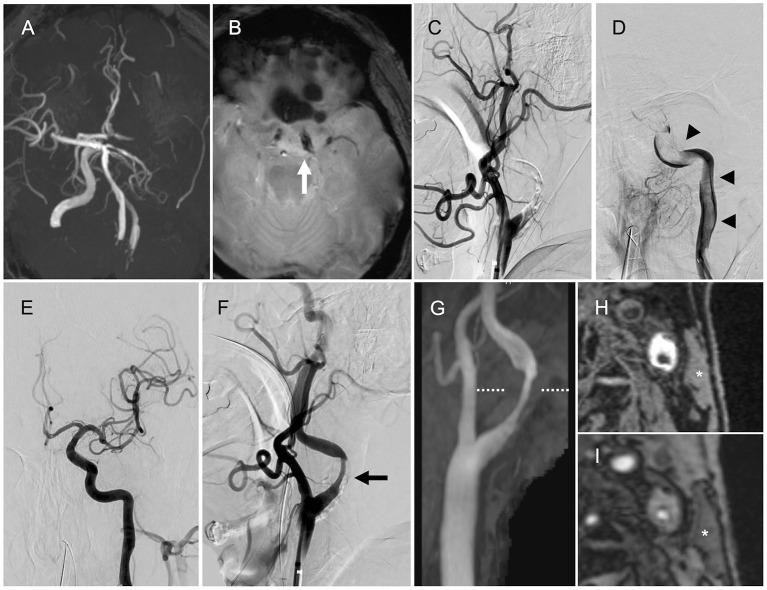

The correlation between the composition of thrombi retrieved by mechanical thrombectomy (MT) and stroke etiology is inconclusive. We describe a case with atherosclerotic components in thrombi retrieved by MT for acute internal carotid artery (ICA) occlusion. A 69-year-old man with acute onset of global aphasia and right hemiplegia was transferred to our institute. His baseline National Institutes of Health Stroke Scale score was 24. Magnetic resonance imaging demonstrated acute ischemic stroke in the left parietal lobe. Magnetic resonance angiography revealed occlusion of the left ICA. MT was attempted for acute left ICA occlusion. The initial angiography showed occlusion of the proximal ICA, while intraprocedural angiography revealed a large thrombus that extended from the cervical ICA to the intracranial ICA. Successful reperfusion was achieved by five passes using stent retrievers and an aspiration catheter. A large volume of red thrombus was retrieved by each pass. The final angiogram showed successful reperfusion with modified Thrombolysis in Cerebral Ischemia grade 2b and severe stenosis in the proximal ICA. Neck magnetic resonance imaging showed severe left ICA stenosis with a vulnerable plaque. Hence, his stroke etiology was determined as large artery atherosclerosis. Histopathological examination of the retrieved thrombi revealed atheromatous components, including cholesterol clefts, foam cells, and a necrotic core. Atherosclerotic components in retrieved thrombi might provide useful clues for diagnosing stroke pathogenesis. Further studies are warranted to clarify the utility of assessing atheromatous components in retrieved thrombi in diagnosing stroke etiology.

机械取栓(MT)取出的血栓成分与卒中病因之间的相关性尚无定论。我们描述了一例通过MT治疗急性颈内动脉(ICA)闭塞取出的血栓中含有动脉粥样硬化成分的病例。一名69岁男性,急性起病,出现完全性失语和右侧偏瘫,被转诊至我院。他的美国国立卫生研究院卒中量表基线评分为24分。磁共振成像显示左侧顶叶急性缺血性卒中。磁共振血管造影显示左侧ICA闭塞。对急性左侧ICA闭塞尝试进行MT治疗。初始血管造影显示ICA近端闭塞,而术中血管造影显示一个大血栓从颈段ICA延伸至颅内ICA。使用支架取栓器和抽吸导管通过五次操作成功实现再灌注。每次操作均取出大量红色血栓。最终血管造影显示再灌注成功,改良脑缺血溶栓分级为2b级,ICA近端严重狭窄。颈部磁共振成像显示左侧ICA严重狭窄伴易损斑块。因此,他的卒中病因被确定为大动脉粥样硬化。对取出的血栓进行组织病理学检查发现了动脉粥样硬化成分,包括胆固醇裂隙、泡沫细胞和坏死核心。取出的血栓中的动脉粥样硬化成分可能为诊断卒中发病机制提供有用线索。有必要进一步研究以阐明评估取出的血栓中的动脉粥样硬化成分在诊断卒中病因方面的效用。